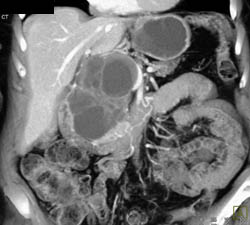

Dilated Pancreatic Duct With Ampullary Mass